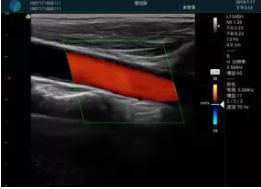

頸動(dòng)脈血流充盈飽滿,無(wú)外溢

肝內(nèi)血管顯示清晰,血流敏感無(wú)外溢